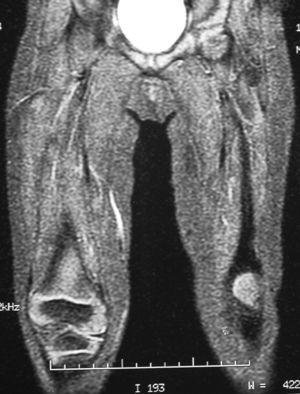

El estudio ecográfico pone de manifiesto una disminución de volumen y alteración de la arquitectura normal de las fibras musculares del vasto intermedio, observándose fundamentalmente en tercio distal un área de mayor ecogenicidad que se interpreta como posible fibrosis (fig. 1).

Figura 1. Ecografía de ambas rodillas en la que se aprecia marcada atrofia del músculo vasto intermedio y un área de mayor ecogenicidad que se interpreta como posible fibrosis.